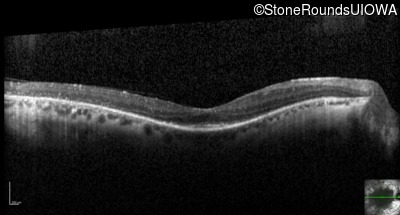

Optical Coherence Tomography - Left - 20/50

Exemplar / OCT Stack

OCT Stack